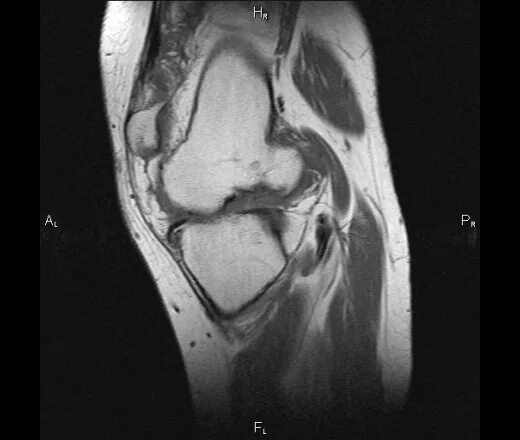

Пигментный виллонодулярный синовит